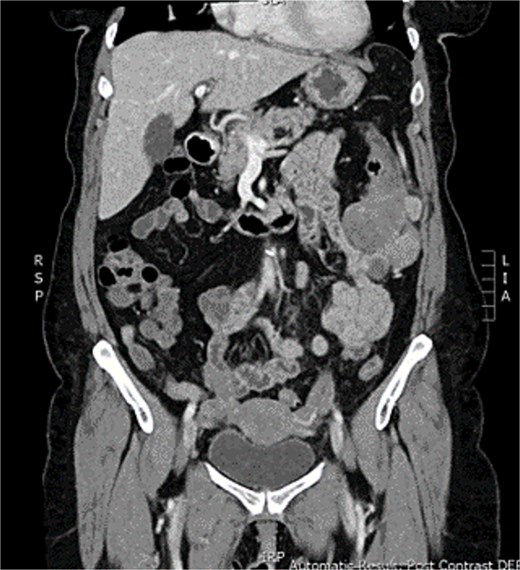

CT abdomen and pelvis was showed uncomplicated diverticulitis; however, a lobulated 54 × 54 mm exophytic mass arising from the transverse colon with adjacent enlarged lymph nodes was incidentally noted (Figs 1 and 2). Colonoscopy, limited by diverticulosis, found no intraluminal mass but revealed desmoplastic mucosal changes at the splenic flexure. Biopsies were nondiagnostic. Staging CT chest showed no metastases, and CEA was 4.0.

CT abomen + pelvis with contrast demonstrating ~5 × 5 cm exophytic lobulated mass at splenic flexure, appearing to arise from transverse colon.